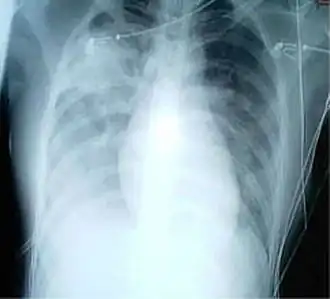

Radiografia ao tórax em que se observa aumento de opacidade em ambos os pulmões, indicativo de pneumonia, em paciente com SARS